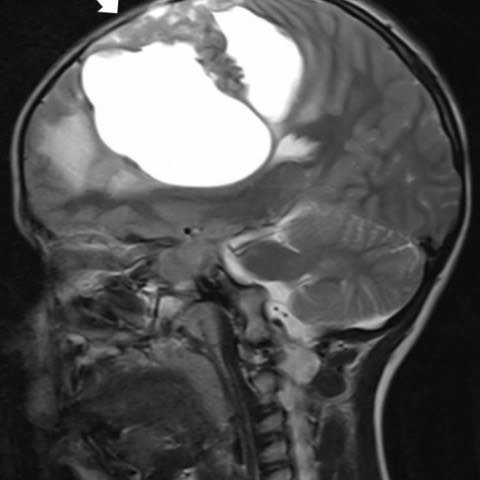

3812. Мальчику 1 года с жалобами на острую правостороннюю моторную слабость выполнена магнитно-резонансная томография, необходимо дифференцировать выявленную рентгенологическую картину с